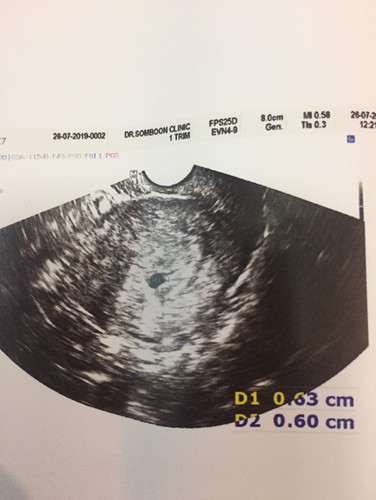

วันนี้ไป รพ.มาค่ะมีอาการเลือดออกทางช่องคลอดสีน้ำตาลอ่อน แต่ไหลกะปริดกระปอยไม่เยอะค่ะเลยไปตรวจอัตราซาวด์ทางช่องคลอด สรุปคือหนูนับตามเนื้อผ้าอายุครรภ์7w6d แต่เครื่องบอกว่าพึ่งเริ่มตั้งครรภ์ ถุงครรภ์แค่0.6cm เล็กมาก มีแม่ๆคนไหนมีประสบการณ์แบบนี้ไหมค่ะ ตอนนี้ท้อง3ค่ะ 2ท้องแรกหลุดค่ะ